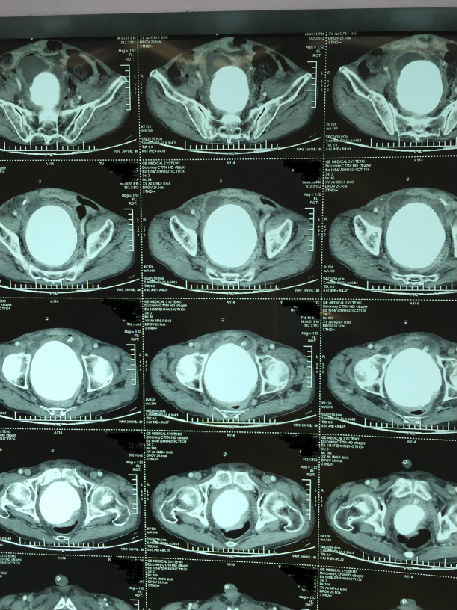

膀胱ct,尿道ct

刘女士盆腔增强ct(红圈内灰色部分均为膀胱肿瘤)

图b:ct,膀胱平滑肌瘤,男,38岁,血尿;膀胱左侧壁见以结节状软组织密度

图14 膀胱结石

膀胱癌ct